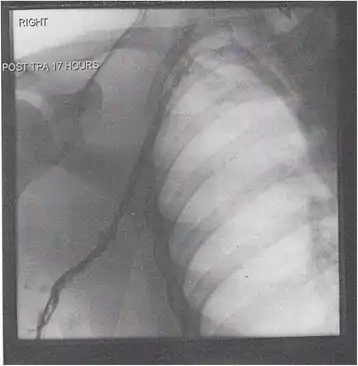

Thrombolysis is the injection of an enzyme into the veins to dissolve blood clots, and while this treatment has been proven effective against the life-threatening emergency clots of stroke and heart attacks, randomized controlled trials[139][140][141] have not established a net benefit in those with acute proximal DVT.[5][142] Drawbacks of catheter-directed thrombolysis (the preferred method of administering the clot-busting enzyme[5]) include a risk of bleeding, complexity,[lower-alpha 12] and the cost of the procedure.[125] Although, while anticoagulation is the preferred treatment for DVT,[125] thrombolysis is a treatment option for those with the severe DVT form of phlegmasia cerula dorens (bottom left image) and in some younger patients with DVT affecting the iliac and common femoral veins.[12] Of note, a variety of contraindications to thrombolysis exist.[125] In 2020, NICE kept their 2012 recommendations that catheter-directed thrombolysis should be considered in those with iliofemoral DVT who have "symptoms lasting less than 14 days, good functional status, a life expectancy of 1 year or more, and a low risk of bleeding."[138]

A mechanical thrombectomy device can remove DVT clots, particularly in acute iliofemoral DVT (DVT of the major veins in the pelvis), but there is limited data on its efficacy. It is usually combined with thrombolysis, and sometimes temporary IVC filters are placed to protect against PE during the procedure.[143] Catheter-directed thrombolysis with thrombectomy[141] against iliofemoral DVT has been associated with a reduction in the severity of post-thrombotic syndrome at an estimated cost-effectiveness ratio of about $138,000[lower-alpha 13] per gained QALY.[144][145] Phlegmasia cerulea dolens might be treated with catheter-directed thrombolysis and/or thrombectomy.[19][143]

- A venogram before catheter-directed thrombolysis for Paget–Schroetter syndrome, a rare and severe arm DVT shown here in a judo practitioner, with highly restricted blood flow shown in the vein

- After treatment with catheter-directed thrombolysis, blood flow in the axillary and subclavian vein were significantly improved. Afterwards, a first rib resection allowed decompression. This reduces the risk of recurrent DVT and other sequelae from thoracic outlet compression.[147]